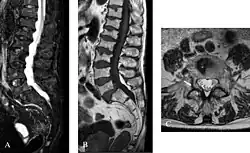

-

Die axiale MRT des Gehirns eines 27-jährigen Morbus-Fabry-Patienten mit ischämischem Schlaganfall zeigt den Schlaganfall in der linken zerebellären Hemisphäre. Der Patient wies sonst keine Symptome der Erkrankung auf. -

Hyperintensitäten der weißen Hirnsubstanz, lakunare Hirninfarkte und Mikroblutungen.

A) Die axiale MRT zeigt vielfältige Läsionen der weißen Hirnsubstanz in der zerebralen Hemisphäre eines 53-jährigen männlichen Patienten mit einem Fazekas-Score von 3.

B) Lakune und Mikroblutungen bei demselben Patienten. -

Die T1-gewichteten sagittalen (A) und axialen (B) MRTs zeigen ein symmetrisch hohes Signal im Thalamus (das sogenannte Pulvinar Sign) eines 66-jährigen männlichen Patienten. (C) und (D), ebenfalls T1-gewichtet, zeigen das Pulvinar Sign bei einem 42-jährigen Patienten. -

Die Time-of-Flight-Magnetresonanzangiographien von vier Morbus-Fabry-Patienten zeigen erweiterte (ekstatische) Blutgefäße (Dolichoektasien der vertebrobasilären Zirkulation).